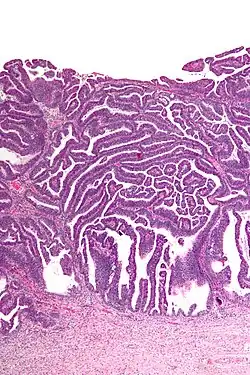

Micrograph of a villoglandular adenocarcinoma the cervix. H&E stain. | |

The name of the lesion describes it microscopic appearance. It has nipple-like structures with fibrovascular cores (papillae) that are long in relation to their width (villus-like), which are covered with a glandular pseudostratified columnar epithelium.

Very low magnification